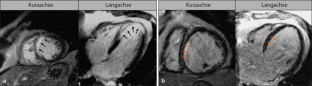

Abb. 2